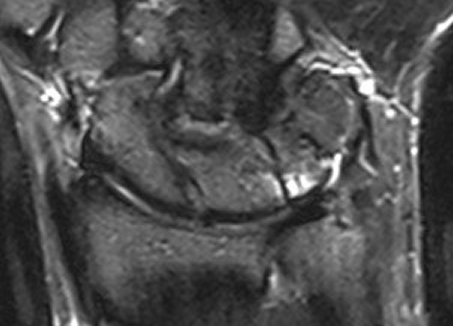

Magnetic Resonance Imaging showed a bone marrow edema adjacent to the fibro-cartilage coalition as well as hyaline cartilage in the distal notch (Figure 3 [Fig. 3], Figure 4 [Fig. 4]).

Figure 3: Magnetic Resonance Imaging of the right wrist in the fluid-sensitive inversion recovery sequence showing bone marrow edema adjacent to the fibro-cartilage coalition

Figure 4: Magnetic Resonance Imaging of the right wrist in the cartilage-sensitive DESS (Double echo steady state) sequence showing hyaline cartilage in the distal notch and fibro-cartilage tissue proximally without cartilaginous coating as typical for luno-triquetral coalition type II of Minaar’s Classification